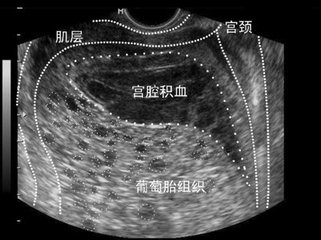

请到家中才了解到,他的颓丧来源于怀孕妻子被检查有宫腔积血,大多人在听到这个名词的时候,脑海中会浮现出一些血淋淋的场景,第一反应就是好严重,怎么办?怎么办?

其实,西柚医生在临床工作中也会碰到早孕期宫腔内有积液的病症,有些孕妇可以从怀孕开始一直维持到妊娠晚期,大小从1厘米到7-8厘米不等,而这些积液大多数是积血。